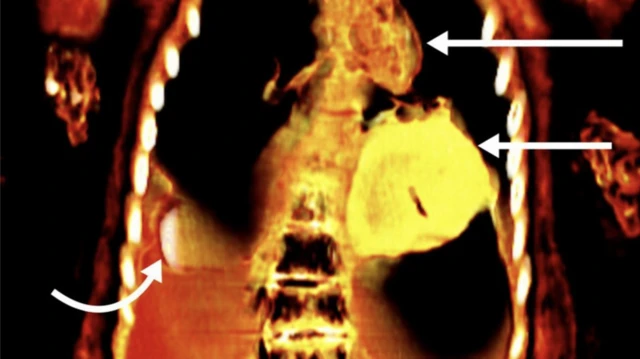

Foto-foto hasil pemindaian menunjukkan di bawah perban-perban yang melapisi tubuh remaja pria terdapat benda sepanjang dua jari yang letaknya di samping alat kelaminnya yang tidak disunat.

Jenazah pria juga memiliki lidah berlapis emas di dalam mulutnya dan jimat emas berbentuk kumbang scarab di bawah toraks.

Tangkapan layar juga menunjukkan tubuh pemuda itu mengenakan sandal dan karangan bunga pakis.